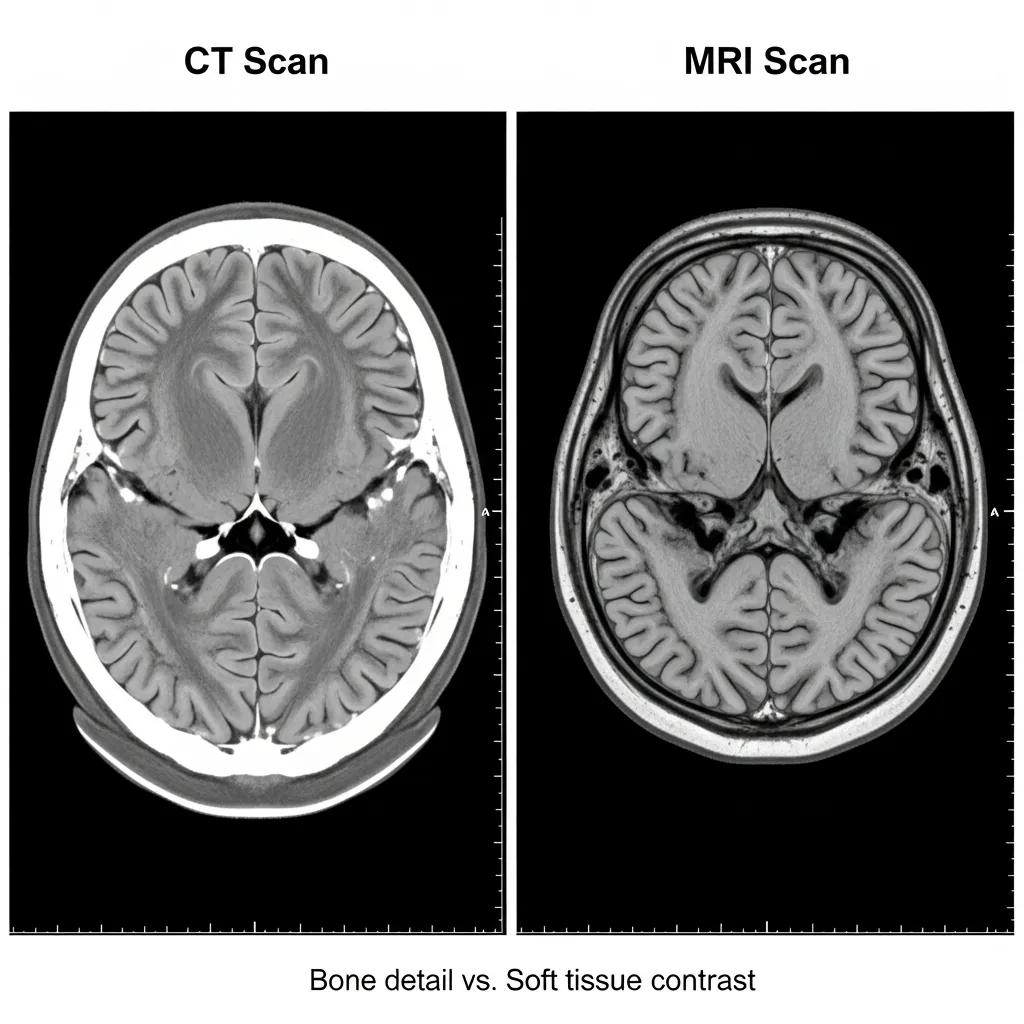

Brain imaging includes several modalities that visualise structure, blood flow and metabolic activity to answer specific clinical questions. Each relies on different physical principles: CT uses X-rays to build fast cross-sectional images, MRI uses magnetic fields and radiofrequency to provide high soft-tissue contrast, and PET uses injected radiotracers to map metabolic or molecular processes. These differences explain why CT is preferred for acute haemorrhage and bone detail, MRI for soft-tissue characterisation and tumour staging, and PET for metabolic or molecular assessment in select cases. The table below summarises key strengths to help match modality to symptom or diagnostic need.

MRI uses magnetic fields and radiofrequency pulses to produce high‑contrast images of brain tissue without ionising radiation, making it ideal for detailed assessment of parenchyma and complex pathology. MRI sequences can be tailored to highlight different tissue properties, detect subtle tumour infiltration, show multiple sclerosis plaques or map structural changes seen in dementia. Scans take longer and are louder than CT and may be unsuitable for patients with certain implants. Gadolinium‑based contrast agents are sometimes used to improve lesion characterisation; clinical teams screen renal function and other contraindications before administration. MRI complements CT rather than replacing it—the choice depends on clinical question and urgency.